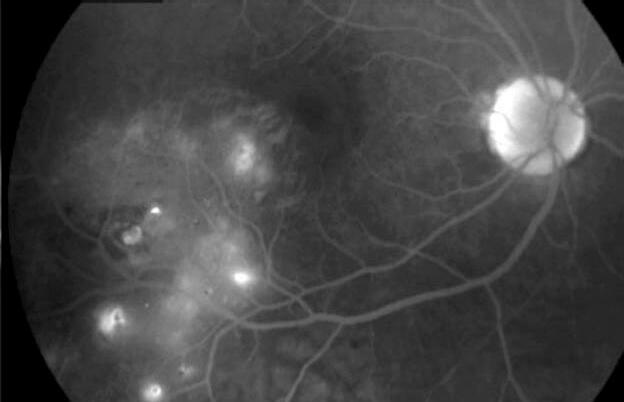

Se solicitó una retinofluoresceinografía (RFG), en la cual se observa: Hiperfluorescencia precoz de las telangiectasias y extravasación tardía.

Referencia foto: (a) hiperfluorescencia precoz de telangiectasias.

Referencia foto: (b) extravasación en tiempo tardío.